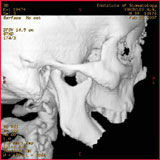

СК томограмма пациента с дефектом нижней челюсти после огнестрельного ранения (а), моделирование замещения дефекта аутотрансплантатом из малоберцовой кости по данным СКТ (б)